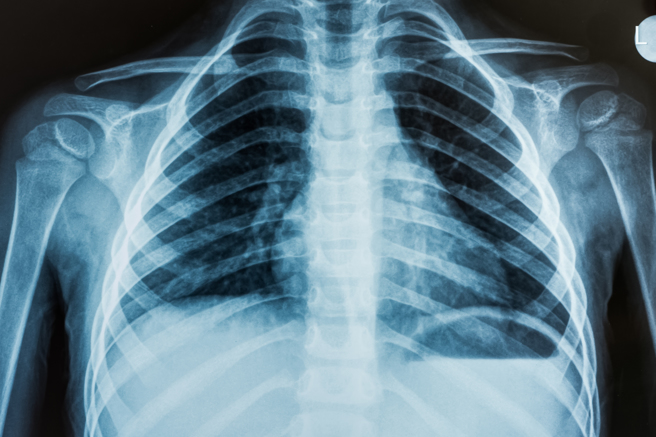

巴西一名患者咳嗽数个月,状况都没有好转,近期到医院就诊,没想到医师检查发现,他的体内竟全都是寄生虫,X光照出数百个白点,看起来像白芝麻,其实是虫卵的钙化残壳,画面让人看了非常惊悚,在网路上引发讨论。

根据《每日邮报》报导,巴西圣保罗州博图卡图(Botucatu)住院医生维克多(Vitor Borin de Souza)日前在推特分享一张X光照,照片中可见患者体内全是白点,原来他感染囊虫病(cysticercosis),是由猪肉絛虫(Taenia solium)幼体所引发的病症,通常是吃了不乾净的食物而摄入虫卵。

维克多表示,只要患者的头部、脊髓或眼睛没有引起感染,大多数情况下,患者都不需要接受特别治疗,照片中白点其实是幼虫钙化的包囊,「牠们不是有活动力的幼虫,如果并未造成身体不适,也无须治疗或处理,生活可以继续过下去」。

维克多进一步说明,寄生虫若跑到脑部,会引起头痛及癫痫,甚至是头晕、脑积水等症状,如果不及时治疗可能会致命,这种情况下通常需动手术切除,若抵达眼部,会导致视力模糊并感染,为了慎重起见,该名患者已被安排接受头部MRI检查。